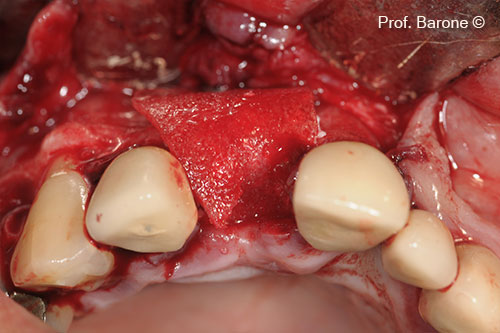

Hình ảnh nhìn từ phía má, răng số 11

Gờ tăng cường

Chuẩn bị vị trí cấy ghép